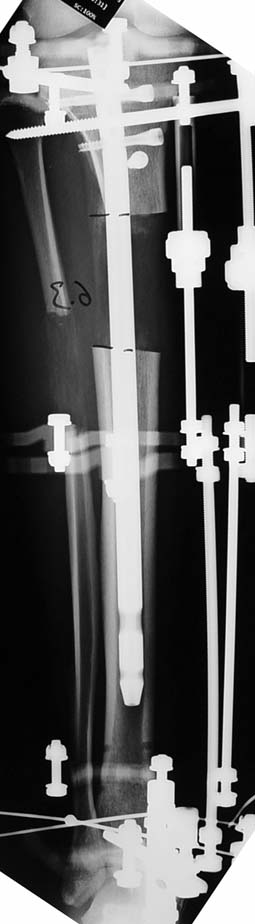

The application of the external fixator: Three Schanz screws are placed distally and three screws are placed proximally. At least 1 mm of distance shall remain between the screws and the nail.

In selected cases, we prefer to use a combination of a unilateral dynamic axial fixator and an interlocked intramedullary nail, in order to protect the length and alignment after the completion of the lengthening procedure. As a prerequisite for this technique, the narowest diameter of the medullary cavity shall be wider than 7 mm and the length of the nail segment distal to the osteotomy site shall be at least 8 cm. after the completion of the lengthening procedure.The intramedullary nail neutralizes shear and bending forces on femur during lengthening, shortens external fixation time, and protects newly formed bone against fractures. In our series, subtrochanteric osteotomy was performed in one case. No varus angulation occured despite the intramedullary nail.

Ilizarov stressed the significance of endosteal blood circulation for distraction osteogenesis. Although we placed the intramedullary nail after reaming the femur in all cases, the time for callus formation was not longer than expected. Thus we found that there is no slowing in the rate of new bone formation due to disruption of medullary blood flow. The rationale of this finding is revascularization that occurs following reaming of the medullary cavity, the fixation stability with the intramedullary nail and early functional weight bearing. The potential disadvantages of a combined use of external and internal fixation metods are increased blood loss, intramedullary infection, risk of fat embolism and excessive metal load.The most fearsome complication is a deep intramedullary infection (panosteomyelitis) triggered by pin tract infection.No such complication was encountered in our series. In order to avoid this complication, after the completion of lengthening the nail shaill be interlocked from the medial side, and contact of internal and external fixator pins shall be avoided.